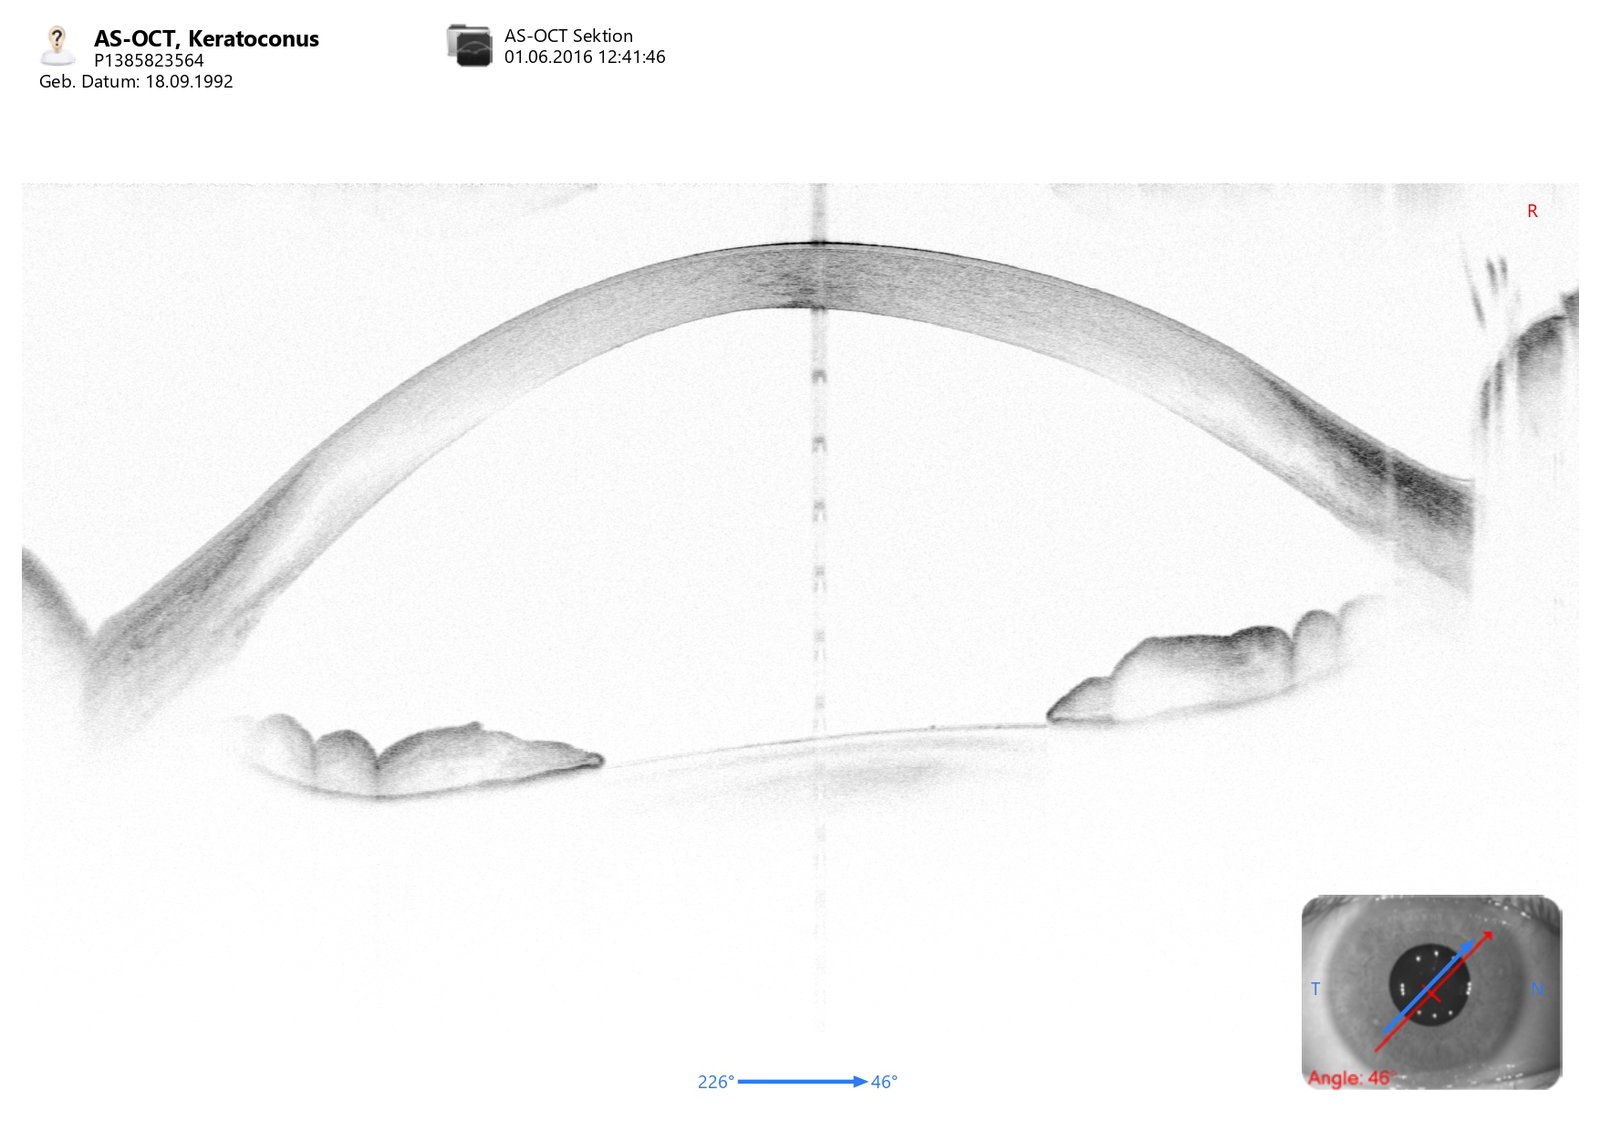

• Keratokonus-Screening zur Abklärung eines Hornhautektasie-Risikos vor einer Hornhautoperation

Une nouvelle classification du kératocône basée sur l’OCT

OCT Basierte Keratokonus Klassifizierung

CSO MS-39 Study Keratoconus screening 2024 ENG